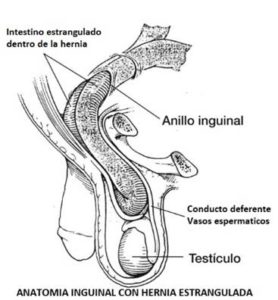

En ocasiones, si la salida de contenido intrabdominal hacia la hernia es excesiva, la gran presión que se crea dentro de la hernia puede hacer que se interrumpa el riego sanguíneo de las vísceras herniadas hasta formarse un infarto intestinal. Es lo que se llama hernia estrangulada e implica una necesidad urgente de cirugía sin demora ya que se trata de una complicación mortal si no recibe el tratamiento adecuado. Aunque por suerte, lo normal es operarse de la hernia de manera programada sin vivir esta dramática situación, es más posible que suceda en aquellos pacientes que decidan demorar la cirugía excesivo espacio de tiempo.

En ocasiones, si la salida de contenido intrabdominal hacia la hernia es excesiva, la gran presión que se crea dentro de la hernia puede hacer que se interrumpa el riego sanguíneo de las vísceras herniadas hasta formarse un infarto intestinal. Es lo que se llama hernia estrangulada e implica una necesidad urgente de cirugía sin demora ya que se trata de una complicación mortal si no recibe el tratamiento adecuado. Aunque por suerte, lo normal es operarse de la hernia de manera programada sin vivir esta dramática situación, es más posible que suceda en aquellos pacientes que decidan demorar la cirugía excesivo espacio de tiempo.